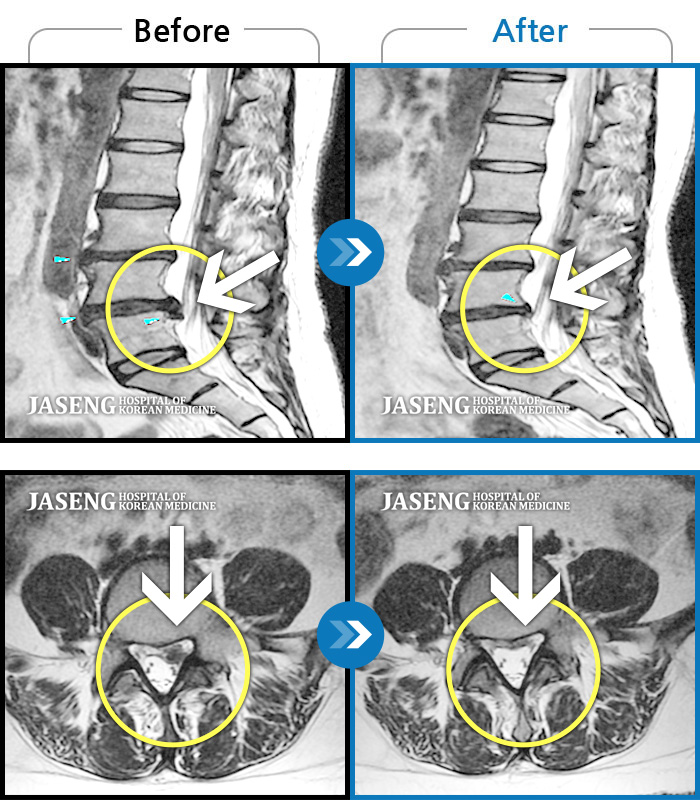

허리디스크

보라매 · 빈상은 원장

허리통증, 좌측 다리 바깥쪽으로 저림이 있어서 양말을 신기도 어려워요.

촬영시기

2022.12.12 ~ 2023.06.10

2023.11.24

조회수 136